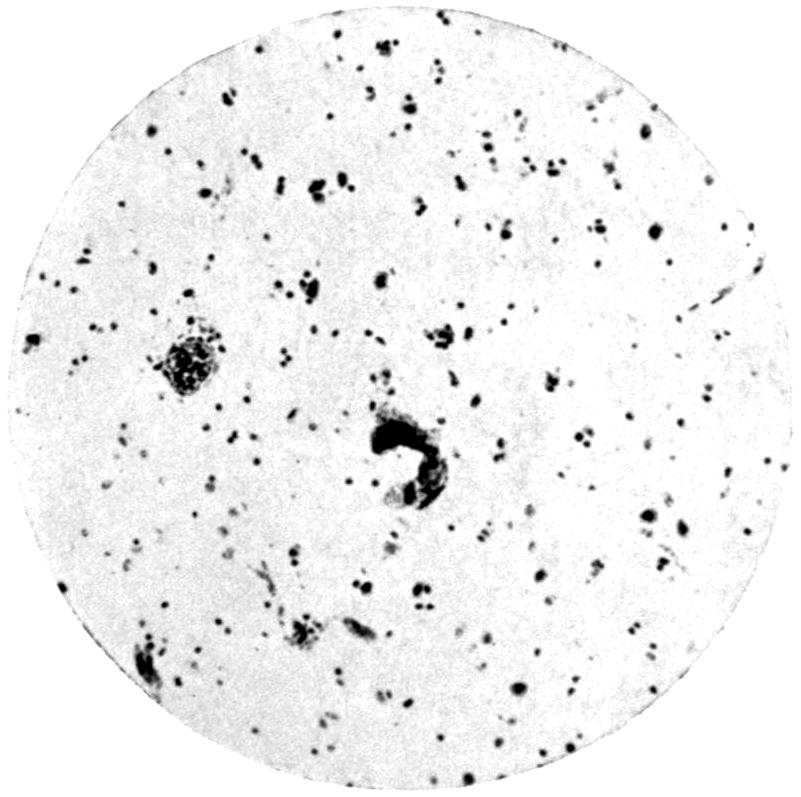

Plate II. 93